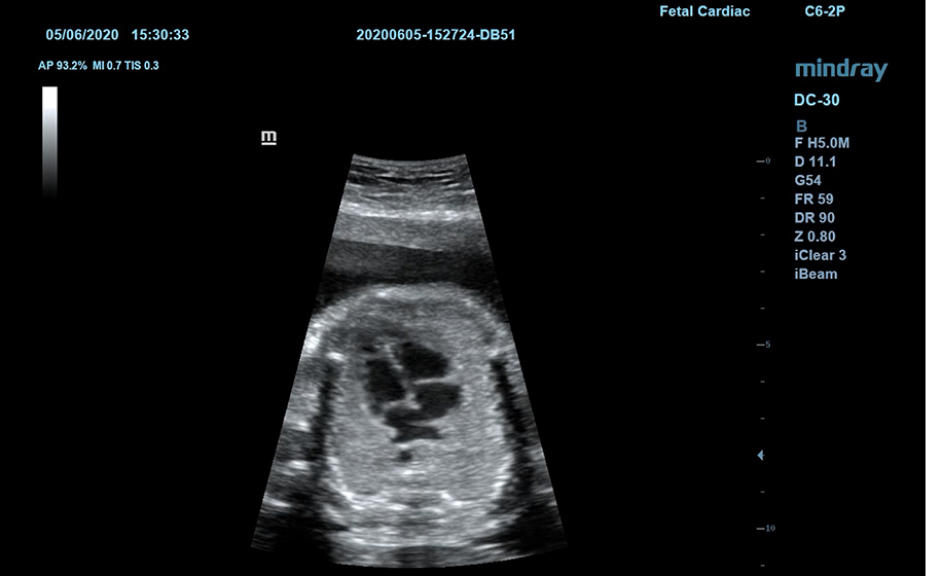

Klinik G?rĂŒntĂŒler